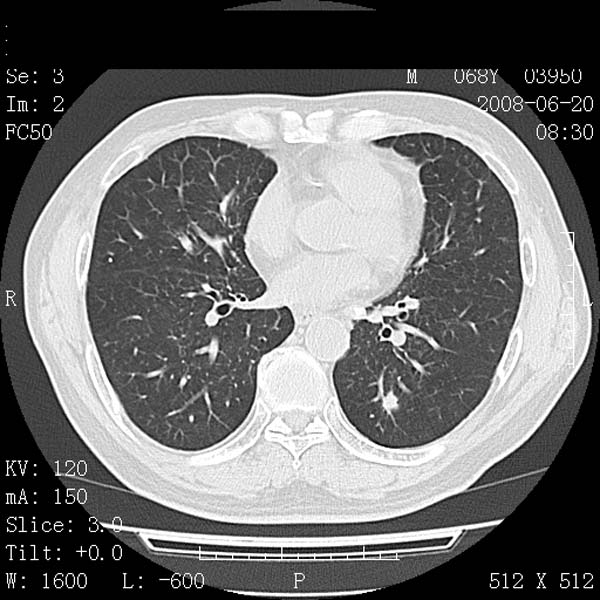

以下是引用守望可可西里在2008-6-24 1:11:00的发言:[br][br] 考虑为周围型肺癌:[br] 1.分叶结节,形态极不规则,蟹足样伸展的恶性浸润特征比较明确。[br] 2.磨玻璃影中由多个更高密度小结节聚集呈梅花瓣样。[br] 3.局部胸膜凹陷征比较明确。[br][br] 另:纵隔胸膜明显增厚、粘连。

以下是引用zjzjr在2008-6-24 11:19:00的发言:[br]支持左下肺周围型肺癌伴右肺转移,纵隔淋巴结转移,心包积液.

以下是引用zhangling在2008-6-24 14:56:00的发言:[br]我们科室意见报告为[br][br]1考虑左下肺周围型肺癌[br]2右肺小结节考虑转移瘤,纵隔淋巴结转移[br]3心包积液. [br] 各位老师分析的相当好 谢意[br]